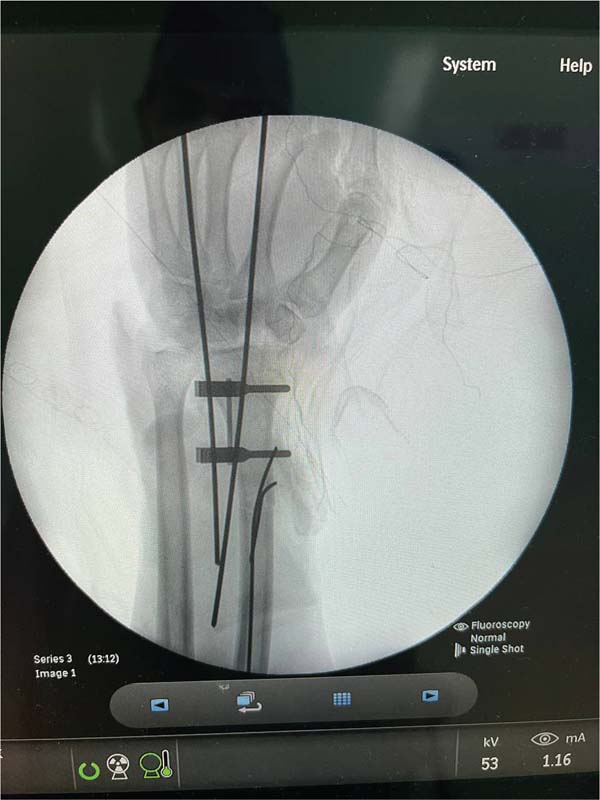

After initial measures according to the Advanced Trauma Life Support (ATLS) protocol, we performed the following surgical steps: vascular stump dissection with identification of the radial and ulnar arteries, and the ulnar and median nerves; heparinization of the blood vessels of the amputated extremity; bone fixation of the radius and wrist block with Kirschner wires; primary microvascular anastomoses of the radial and ulnar arteries and three dorsal veins; suture of the median and ulnar nerves under microscope guidance; and, finally, an en bloc flexor tenorrhaphy and skin grafting over the wound due to tissue loss (►Figs. 4-7).4

The patient presented with good hand perfusion and required temporary immobilization due to the fragility of the anastomoses. Pulse oximetry was monitored during hospitalization. The patient was cooperative throughout the admission, leading to a better outcome. After 10 days under observation, the patient was discharged from the hospital with instructions for care and outpatient follow-up (►Fig. 8).